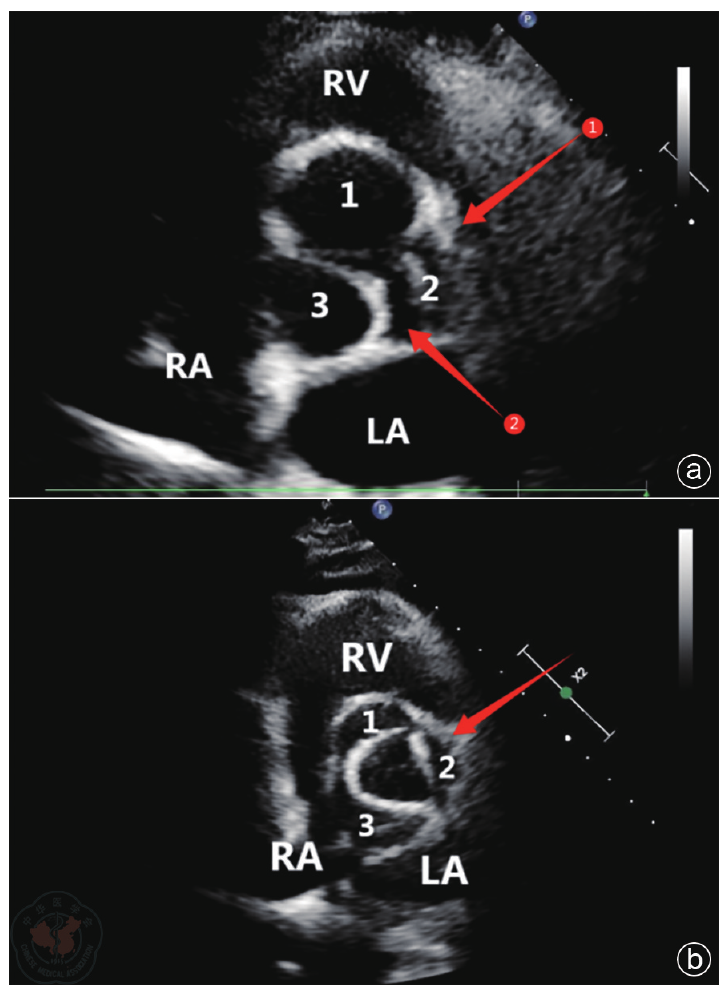

Methods The diagnosis and treatment data of one patient with severe AI admitted to the Air Force Medical Center on October 29, 2025, were retrospectively analyzed. Preoperative echocardiography was used to accurately assess valve structure (including number, morphology, echogenicity, etc.), the cause of regurgitation (including valve calcification, prolapse, perforation, annular dilatation, etc.) and its severity (including the ratio of regurgitant jet width to left ventricular outflow tract width, regurgitant area and length, Doppler spectra, etc.). Key aortic root dimensions were measured (including valve orifice area, aortic annulus, sinus of Valsalva, sinotubular junction, and ascending aortic diameters) to provide a basis for selecting the appropriate J-VALVE TF prosthesis size. Intraoperative ultrasound served as a real-time " navigation" system, guiding the entire process of device delivery and deployment, and providing immediate assessment of prosthesis position, function, and the presence of paravalvular leakage. Postoperative ultrasound served as the primary follow-up tool to evaluate prosthetic valve function and cardiac chamber reverse remodeling.

Results The patient experienced chest tightness and shortness of breath one year prior while lying flat at night. Symptoms could be induced by exertion or insomnia, lasted approximately one minute, and could be relieved by taking a deep breath. Echocardiography indicated: aortic developmental anomaly, aortic valve insufficiency with massive regurgitation, dilatation of the aortic sinus, and widening of the ascending aorta. Based on clinical presentation and echocardiographic findings, the patient underwent TAVR using the J-VALVE TF valve system. Intraoperative ultrasound provided real-time guidance during the delivery and deployment of the J-VALVE TF valve, monitoring the deployment process and the relative position of the delivery system. It was used to assess potential impacts on the mitral valve and coronary ostia before deployment and to evaluate prosthetic valve function after deployment. Postoperative assessment focused on the presence of paravalvular leakage, cardiac function, and the recovery of cardiac chamber geometry.